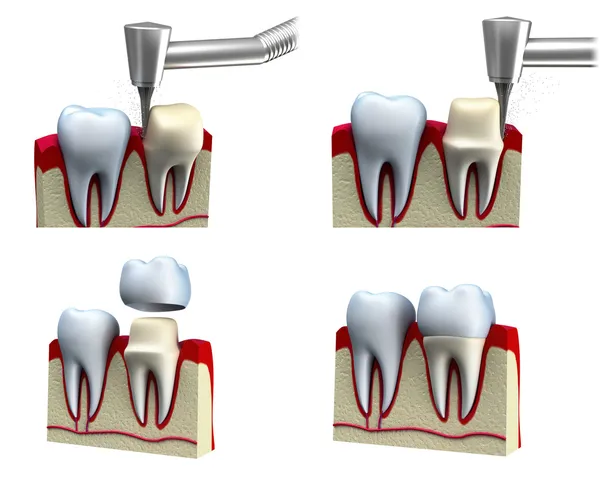

1. Examen et Préparation :

Le dentiste examine la dent endommagée et détermine si une couronne est nécessaire. Lors du premier rendez-vous, il prépare la dent en retirant une partie de la structure dentaire existante pour créer de l'espace pour la couronne.

4. Cimentation :

Lors du deuxième rendez-vous, la couronne permanente est cimentée en place après avoir été ajustée pour assurer un bon ajustement et une occlusion appropriée.